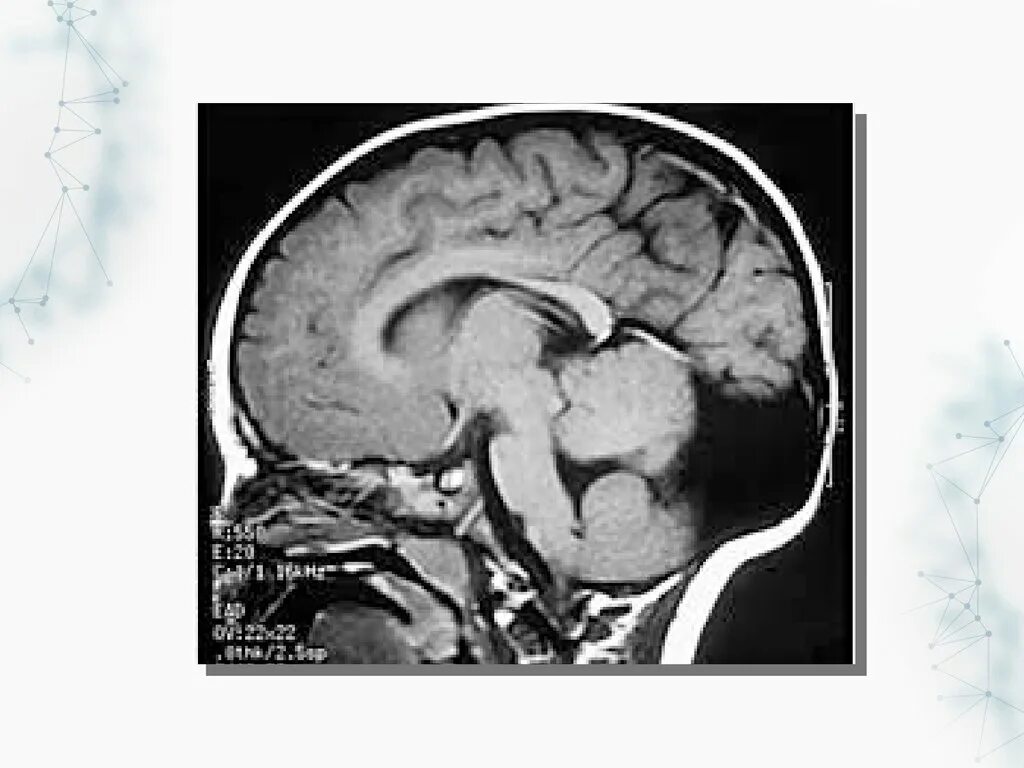

Денди уокера мрт